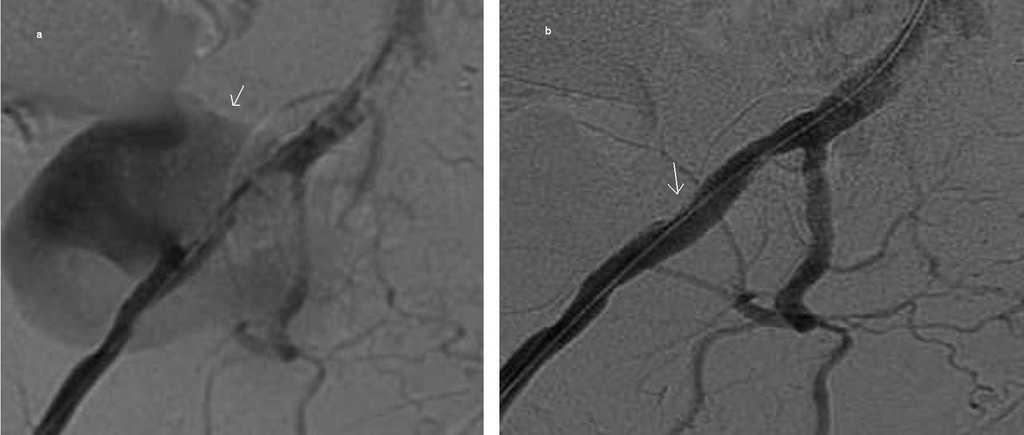

Figura 3. Pseudoaneurisma dependiente de la arteria ilíaca externa antes (a) y después (b) de la reparación endovascular.

En mayo de 2009 presenta dolor brusco y tumoración pulsátil en región inguinal derecha, observando en eco-Doppler y angio-tomografía axial computarizada una imagen sugerente de pseudoaneurisma dependiente de la AIE, en situación teórica de la anastomosis del injerto renal previo (figura 1).

Se deriva a Cirugía Vascular para reparación del pseudoaneurisma que se origina en la anastomosis con la arteria renal del riñón trasplantado. Se repara sin incidencias de forma endovascular, implantando prótesis ilíaca tipo Zenith, con fenestraciones para preservar ramas viscerales (figura 2), obteniendo buen resultado radiológico (figura 3) y clínico.